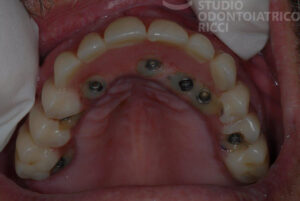

In determinati casi selezionati, è possibile applicare la protesi provvisoria lo stesso giorno dell’intervento implantare. Questa tecnica, chiamata carico immediato, viene spesso impiegata:

In riabilitazioni estese (es. arcata completa)

In aree con elevata valenza estetica (zona frontale)

In pazienti con buone condizioni ossee e generali

Il vantaggio principale è la rapidità del risultato estetico e funzionale, mantenendo comfort e sicurezza.